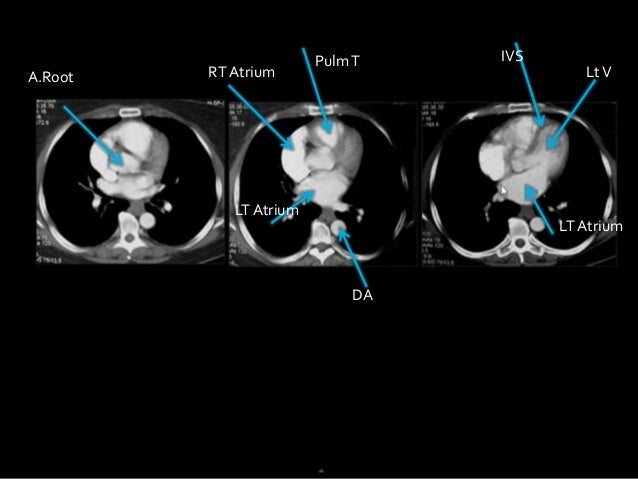

Ct thorax anatomy. Anatomy of the heart quiz ct click on the image description. Anatomy of the thorax lungs and mediastinum ct interactive atlas of human anatomy using cross sectional imaging we have created an anatomical atlas of the chest and the mediastinum which is an interactive tool for studying the cross sectional anatomy of the normal thorax based on an enhanced multidetector computed tomography with helical angiography of the thorax axial plane. This photo gallery presents the anatomy of the chest by means of ct axial reconstructions mediastinal window.

5 thoracic vertebra 6 rib 11 oesophagus 13 upper lobe of left lung 15 lower lobe of left lung 18 middle lobe of right lung 19 lower lobe of right lung 29 descending thoracic aorta 31 azygos vein 35 left atrium 36 right atrium 37 left ventricle. This mri chest thorax axial cross sectional anatomy tool is absolutely free to use. Atlas of chest ct mediastinal window.

Click on different parts of the heart and coronary vessels on this axial ct and answer corresponding questions. Use the mouse scroll wheel to move the images up and down alternatively use the tiny arrows on both side of the image to move the images on both side of the image to move the images. Radiology basics of chest ct anatomy with annotated coronal images and scrollable axial images to help medical students and junior doctors learning anatomy.